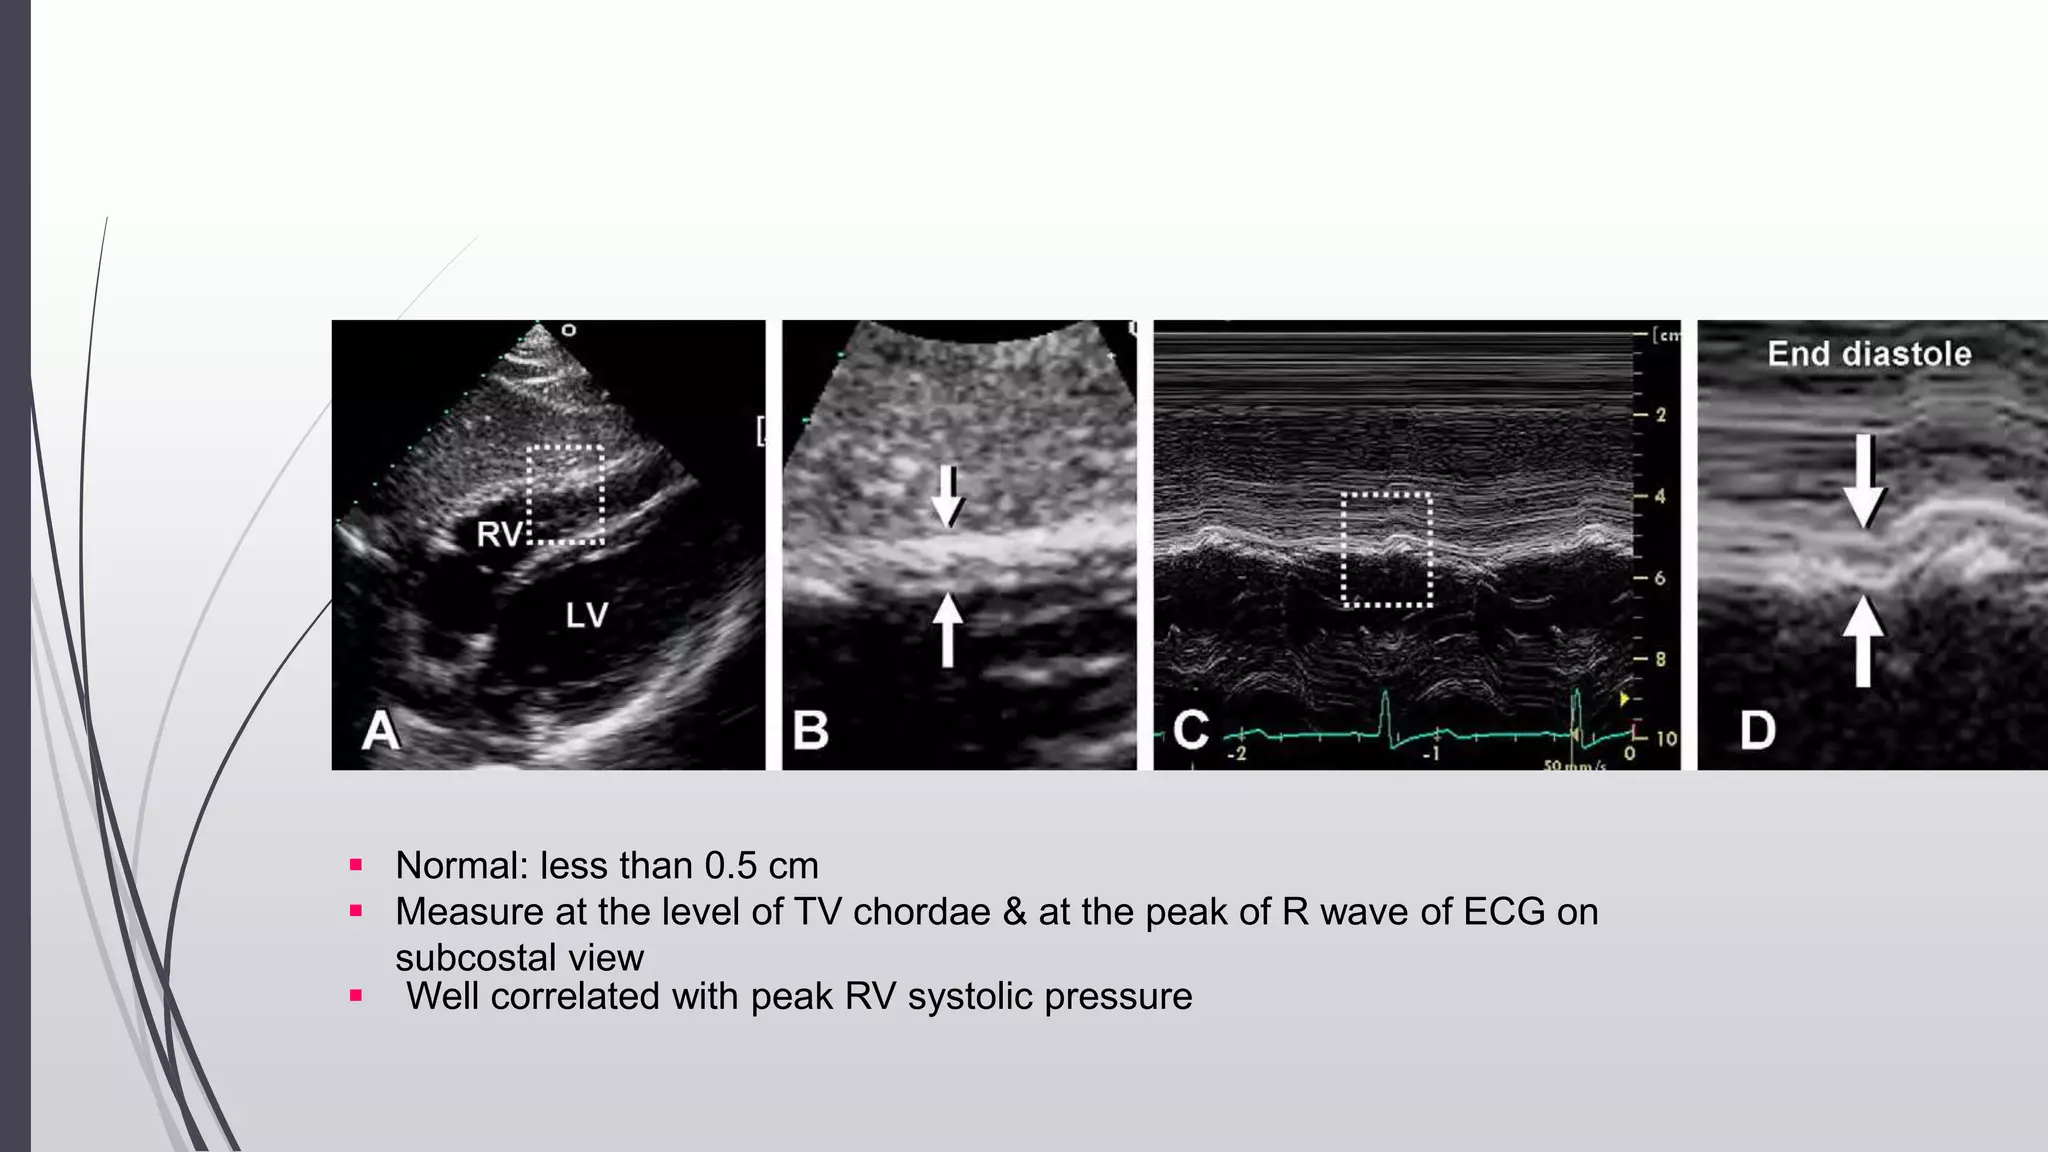

RV Wall Thickness

Useful measurement for RVH (Pressure overload)

 ↑RV wall thickness - can be seen in infiltrative and

hypertrophic cardiomyopathies

Measured at end-diastole by m-mode or 2d echo from the

subcostal window, preferably at the level of the tip of the

anterior tricuspid leaflet or left parasternal windows

when there is significant thickening of the visceral

pericardium, measurement of the RV wall may be

challenging.

Certain conditions are associated with RV wall thinning -

ARVD

No accepted echo criteria to define an abnormally thin

RV wall.

 Normal: less than 0.5 cm

 Measure at the level of TV chordae & at the peak of R wave of ECG on

subcostal view

 Well correlated with peak RV systolic pressure